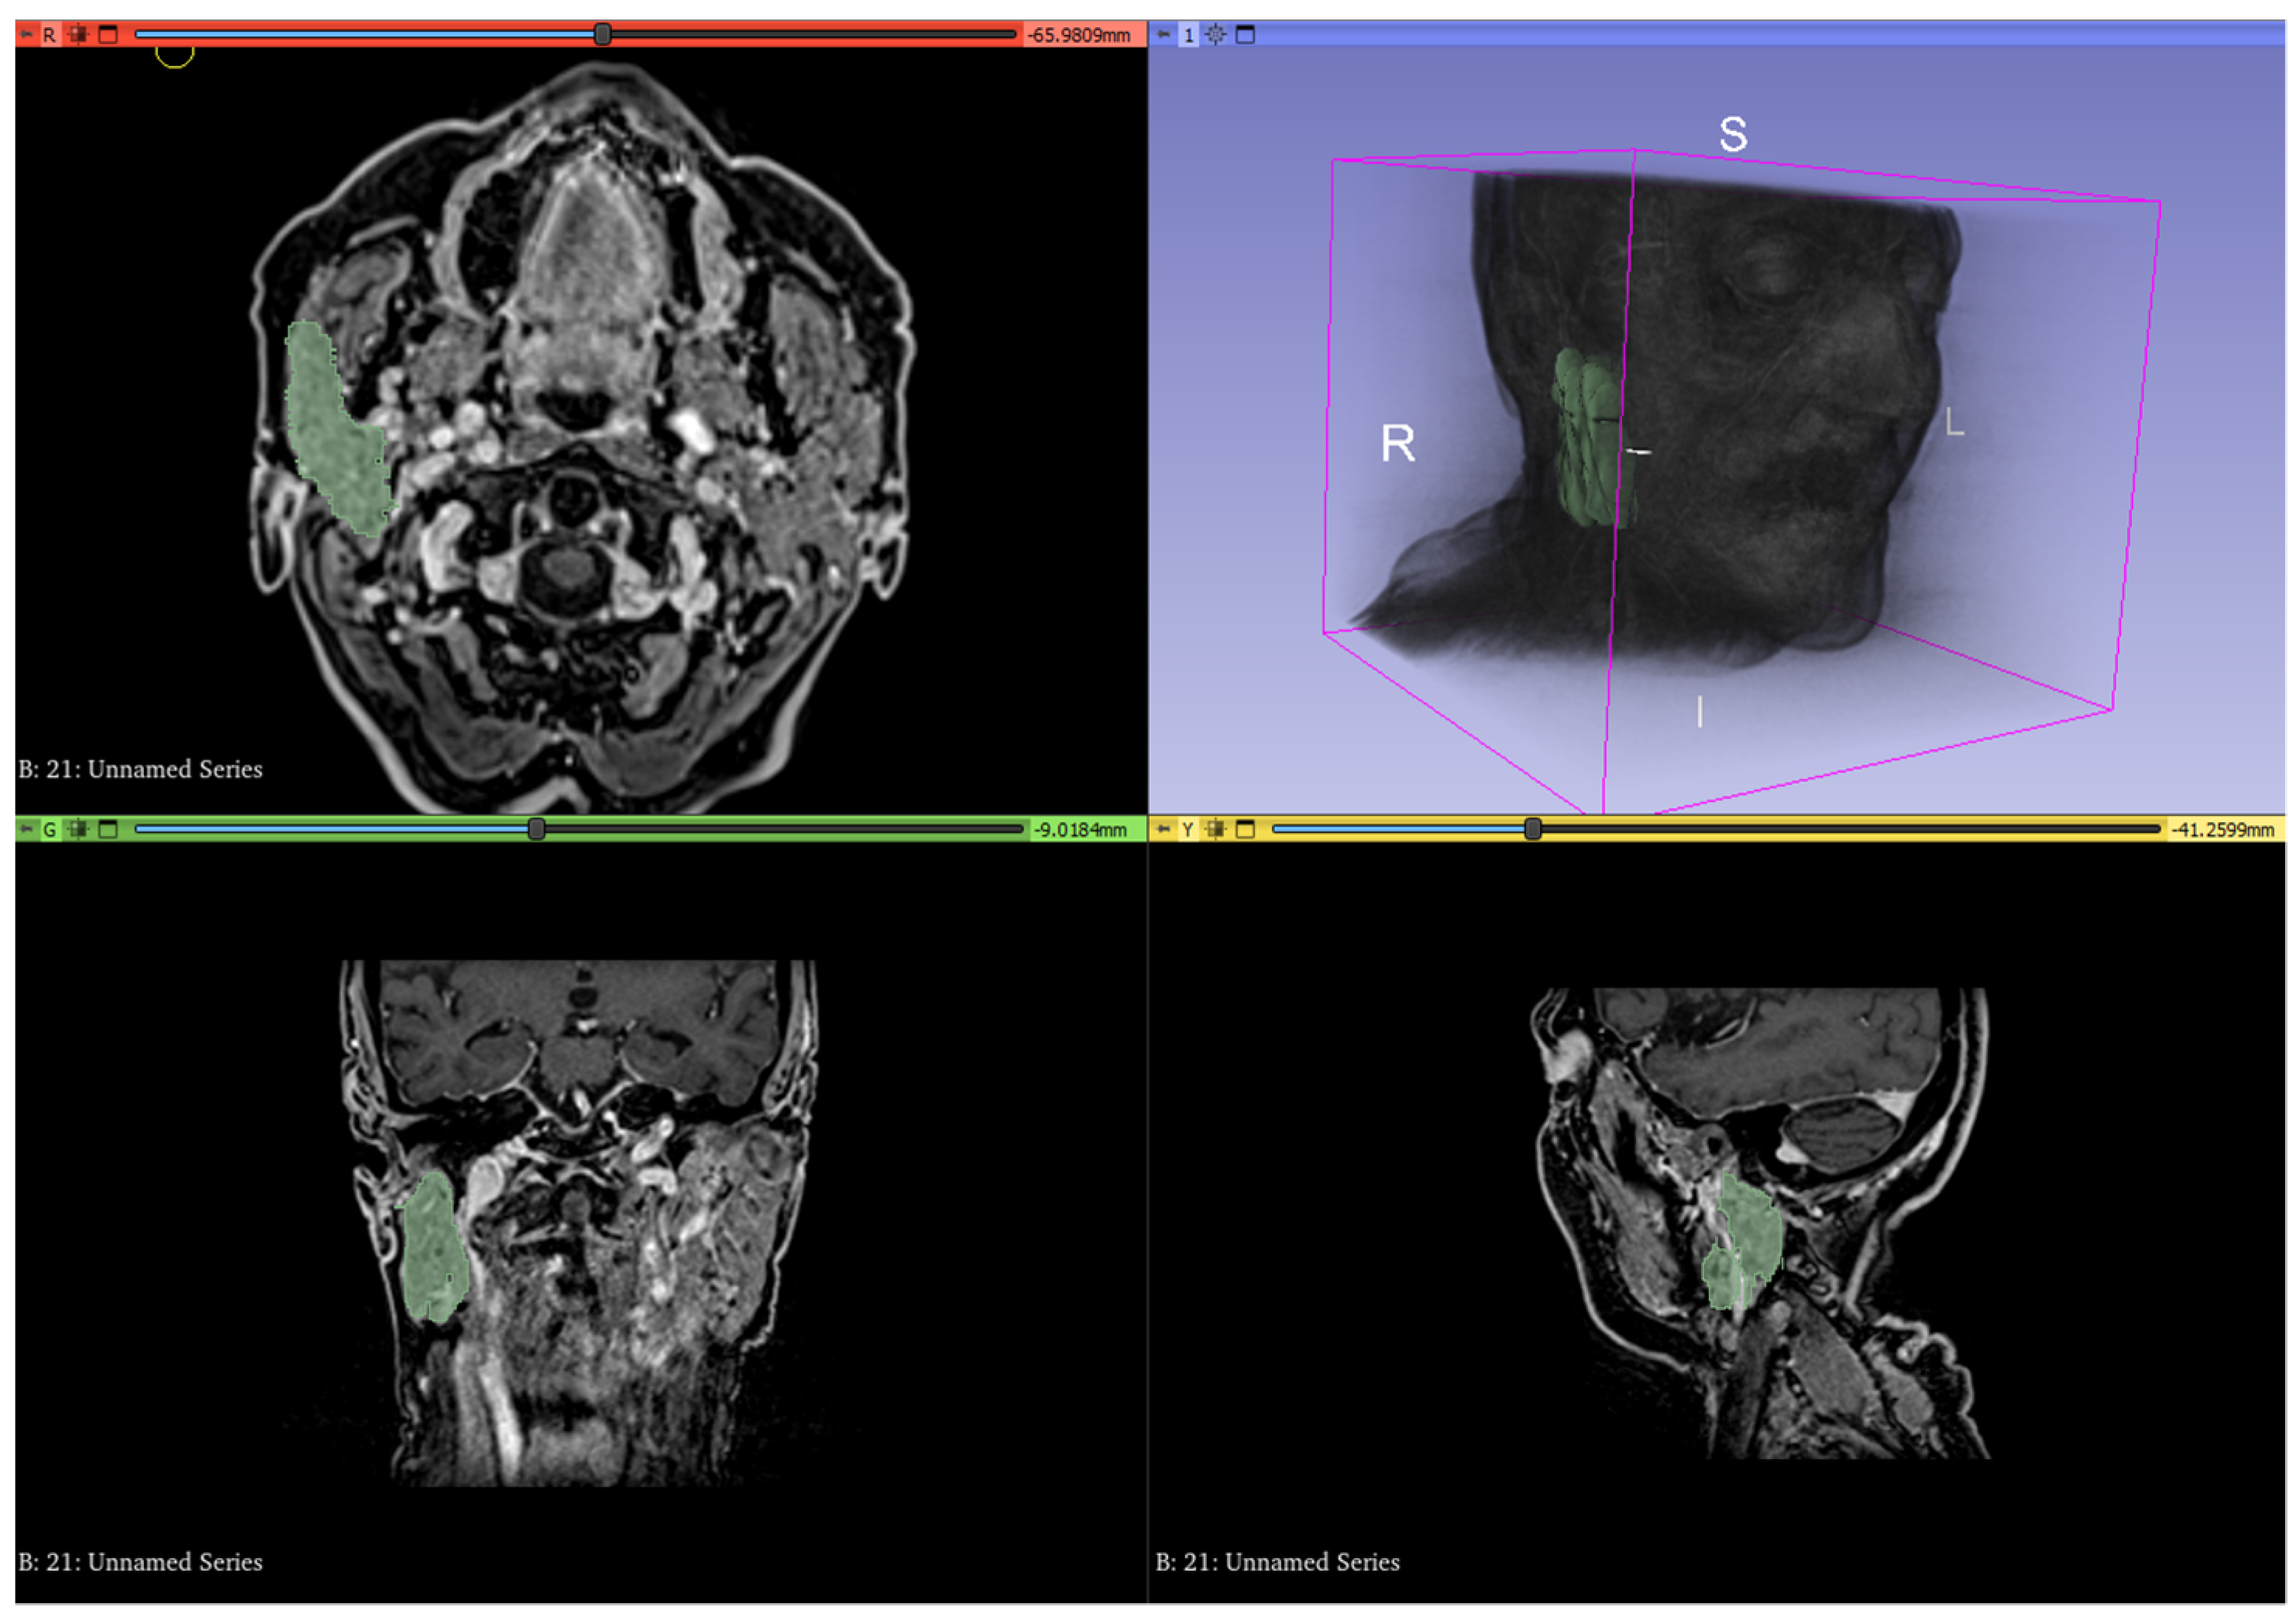

2.3. Image Acquisition and Analysis

- T2 signal intensity (SI) hyper-, iso-, or hypointense with respect to the muscle signal of the parotid and submandibular glands before and after RT;

- SI hyper- or hypointense of the parotid and submandibular glands before and after RT on DWIb800 images;

- Mean ADC values of the parotid and submandibular glands before and after RT (ADC pre-post) on DWI sequences;

- Mean AUC and K(trans) values of the parotid and submandibular glands before RT (AUCpre, K(trans)pre) and after RT (AUCpost, K(trans)post) on DCE-PWI sequences;

- Ratio between AUC values of parotid and submandibular glands before and after RT (AUCpost/pre);

- Ratio between K(trans) values of the parotid and submandibular glands before and after RT (K(trans)post/pre).